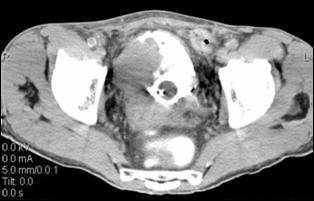

4.3. Tomografia computerizata si rezonanta magnetica nucleara

Informatiile furnizate de aceste metode moderne imagistice ridica procentajul acuratetei diagnostice pana la 85% in aprecierea infiltratiei parietovezicale a tumorilor (T) si la circa 90% pentru decelarea adenopatiei pelviene.

Figura 37. Aspect

tomografic de tumora vezicala. Formatiune tumorala

exofitica protruziva intravezical situata pe peretele

postero-lateral stang. Figura 38. CT pelvin - Tumora voluminoasa in hemivezica

dreapta Figura 39. CT abdominal - Adenopatie extraregionala